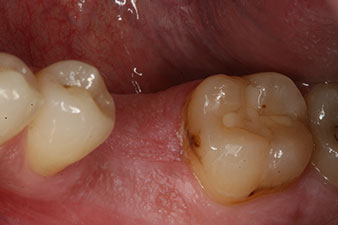

Abformung

Abb. 8: Es folgt die Abformung für die definitive Krone.

Damit konnten eine erfolgreiche Osseointegration und ausreichende biologische Stabilität dokumentiert werden, die eine Abformung in derselben Sitzung erlaubte.

Die Abschlussbilder zeigen die verschraubte monolithische Kompositkrone in situ und die Röntgenkontrolle (Abb. 9 und 10) (6).